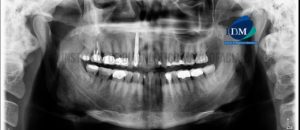

Paciente masculino de 48 años de edad, es referido al Instituto de Diagnóstico Maxilofacial – IDM para evaluación tomográfica de la pieza 17. A la